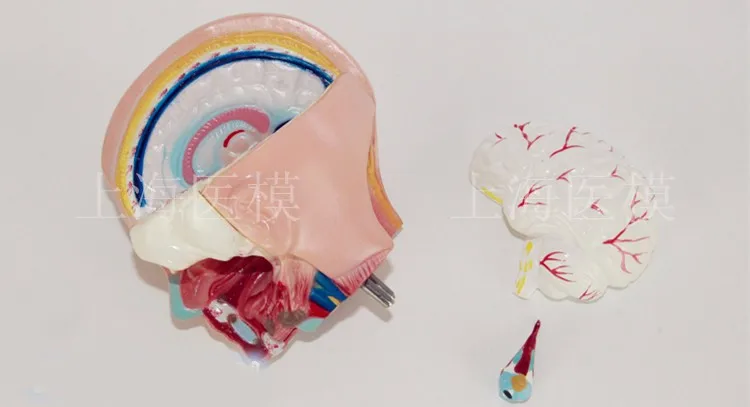

45CM uniex human Torso human anatomical structure model internal organ model 23 parts